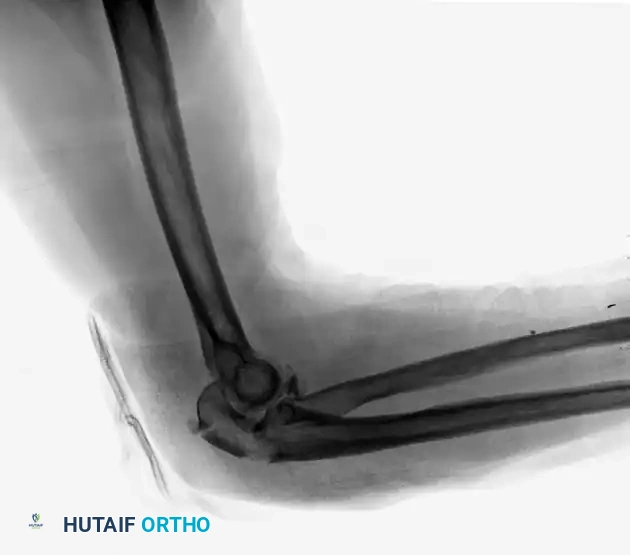

Complex Fracture-Dislocation of the Elbow (Pre-op AP):

Complex Fracture-Dislocation of the Elbow (Pre-op Lateral):

Fixation with Multiplanar Locking Intramedullary Nail (Post-op AP):

Fixation with Multiplanar Locking Intramedullary Nail (Post-op Lateral):